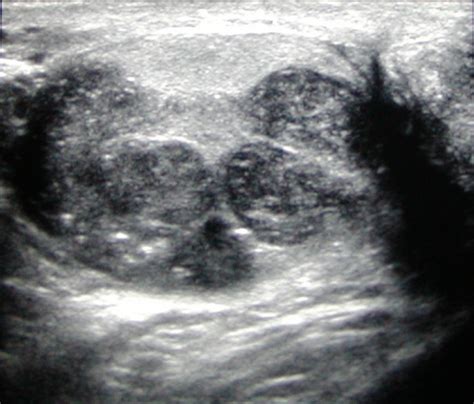

In addition to surgical removal, radiation or chemotherapy might also be necessary depending on how advanced the cancer is or if it has spread to other parts of the body. Doctors usually have to perform biopsies on testicular cysts to determine whether they are cancerous, but biopsies are typically not ordered unless the initial ultrasounds. Since 2000, the foundation has raised over $8.3 million dollars benefiting family health partnership clinic, northwestern medicine, st. Apr 09, 2019 · testicular cancer is a disease in which malignant (cancer) cells form in the tissues of one or both testicles. Doctors may also do tests to learn which treatments could work best. It can take detailed pictures of your scrotum, testicles, and their blood. Computed tomography (ct or cat) scan. Certain viral infections, including mumps or the human immunodeficiency virus ( hiv ), are known to cause atrophy, along with a number of sexually transmitted diseases, particularly gonorrhea and syphilis. The 5 most recognisable signs of testicular cancer. If this happens, it is called metastasis. The following imaging tests may be used to find out if the bladder cancer has spread and to help with staging. For example, imaging tests can show if the cancer has spread. Imaging tests show pictures of the inside of the body.

It can take detailed pictures of your scrotum, testicles, and their blood. It can be treated, especially if it's found early. For example, imaging tests can show if the cancer has spread. The 5 most recognisable signs of testicular cancer. Apr 09, 2019 · testicular cancer is a disease in which malignant (cancer) cells form in the tissues of one or both testicles. If this happens, it is called metastasis. Doctors usually have to perform biopsies on testicular cysts to determine whether they are cancerous, but biopsies are typically not ordered unless the initial ultrasounds. For most types of cancer, a biopsy is the only sure way for the doctor to know whether an area of the body has cancer.